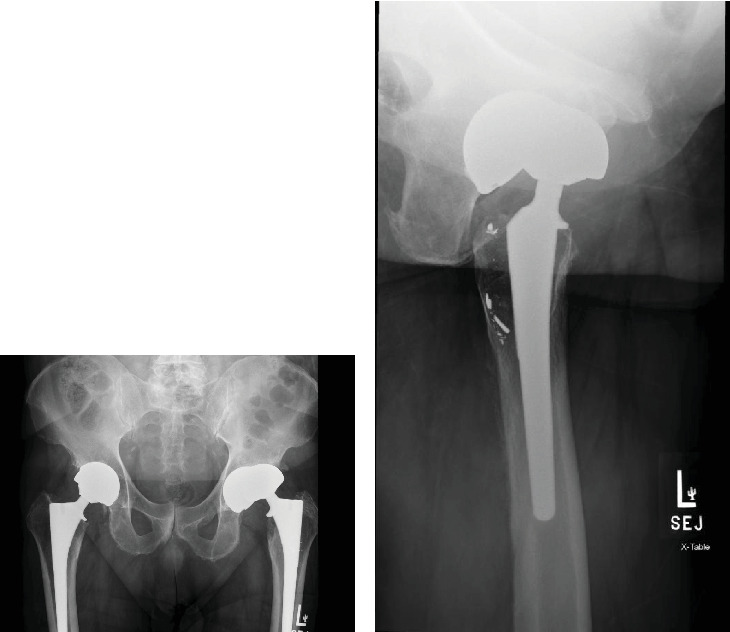

Introduction: Total hip arthroplasty (THA) is a commonly performed and highly successful surgical procedure. Metal-on-metal (MoM) THA implants were introduced two decades ago and subsequently recalled due to high early revision rates. Acetabular cup erosion and fragmentation secondary to chronic edge loading causing delayed instability are rare but devastating complications of MoM THA warranting expeditious revision surgery. Case Presentation: We report a 70-year-old male with a history of bilateral MoM THA who presented with left hip instability. In addition to the radiographic and clinical features of hip instability, macroscopic examination at revision surgery revealed extensive erosion and fragmentation of the antero-superior margin of the implanted cup, osteolysis, and widespread metallosis of the periarticular soft tissues. Discussion: This case highlights a significant adverse complication of MoM THA. Despite the industry's wide discontinuation and recall of these implants, MoM hip arthroplasty implants are present in many patients, who are all at risk of developing similar complications. Guidelines for the surveillance and treatment of both symptomatic and asymptomatic MoM THAs have been reported, although ambiguity remains in the optimal approach for managing patients with existing MoM THA. Conclusion: Failure of MoM hip arthroplasty is most commonly the result of adverse reaction to metal debris. We present a novel mechanism of failure in a patient presenting with late instability due to asymmetric wear of the MoM bearing surface.. While it is uncertain whether early intervention in this patient may have prevented this complication, arthroplasty surgeons should be aware of the various modes of failure for MoM hip implants, as expeditious revision surgery is often required.

全髋关节置换术(THA)是一种常见且非常成功的外科手术。金属对金属(MoM) THA植入物在20年前引入,随后由于早期翻修率高而被召回。髋臼杯糜烂和骨折继发于慢性边缘负荷导致迟发性不稳定是罕见的,但毁灭性的并发症需要快速翻修手术。病例介绍:我们报告一位70岁男性,有双侧MoM THA病史,表现为左髋关节不稳定。除了髋关节不稳定的影像学和临床特征外,翻修手术时的宏观检查显示植入杯前上缘广泛糜烂和碎裂,骨溶解,关节周围软组织广泛金属化。讨论:本病例强调了MoM THA的一个重要的不良并发症。尽管业界广泛停止和召回这些植入物,MoM髋关节置换术植入物存在于许多患者中,他们都有发生类似并发症的风险。有报道了有症状和无症状MoM THA的监测和治疗指南,尽管对于现有MoM THA患者的最佳治疗方法仍然不明确。结论:MoM髋关节置换术失败最常见的原因是金属碎片的不良反应。我们提出了一种新的失败机制,在病人表现出晚期不稳定,由于不对称磨损的MoM承载表面。虽然尚不确定该患者的早期干预是否可以预防这种并发症,但关节置换外科医生应该意识到MoM髋关节植入物的各种失败模式,因为通常需要快速翻修手术。